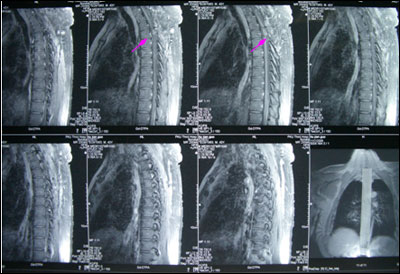

胸髓内血管网织细胞瘤(外院术后)

男性,43岁,14年前无诱因出现左下肢无力、走路不稳,渐加重并延至右下肢。9年前在外院行手术治疗,病理为“海绵状血管瘤”,术后感觉、运动功能恶化,需扶拐行走,且感觉、运动障碍日渐加重,后期伴发皮肤烫伤、便秘、小便失禁,生活质量严重下降。

术前图片:

手术在显微镜下进行,术中完整切除髓内桑椹样肿瘤,术后患者可自己翻身,部分感觉恢复,生活质量较术前明显改善。术后病理回报为海绵状血管瘤。